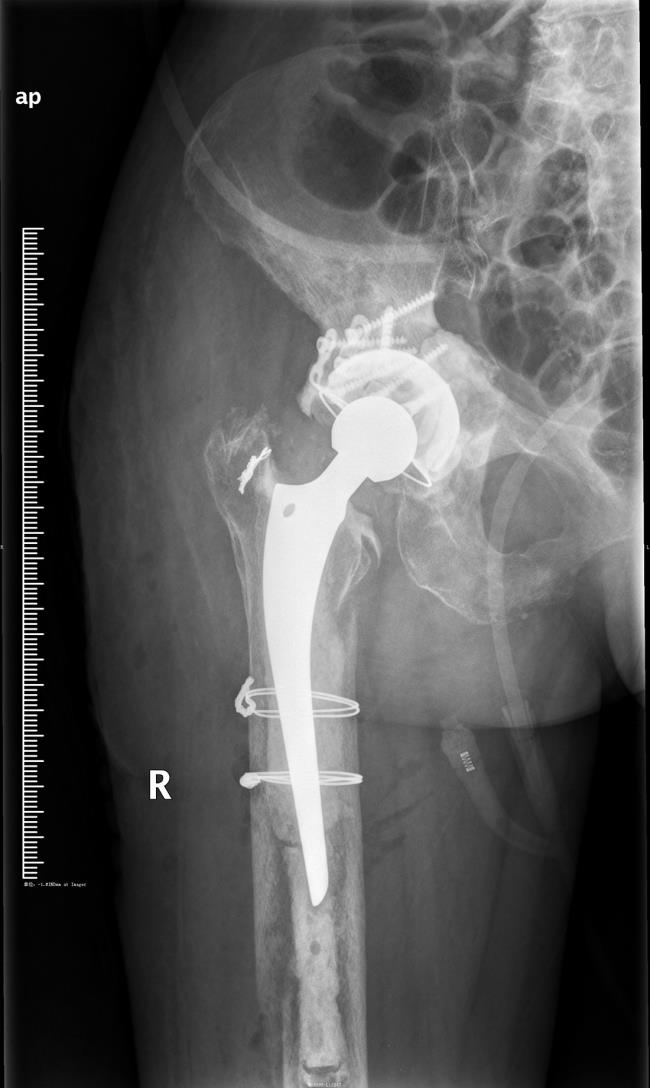

病例1:女,74岁,因右股骨颈骨折在外省某医院做人工全髋关节置换手术,术后由于右髋关节疼痛,活动障碍,严重影响生活,在床上敞了一年多,后转到我科治疗。

经我科行人工关节翻修手术,术后疼痛缓解,活动功能恢复,3个月后复查患者已能下地活动,效果满意。